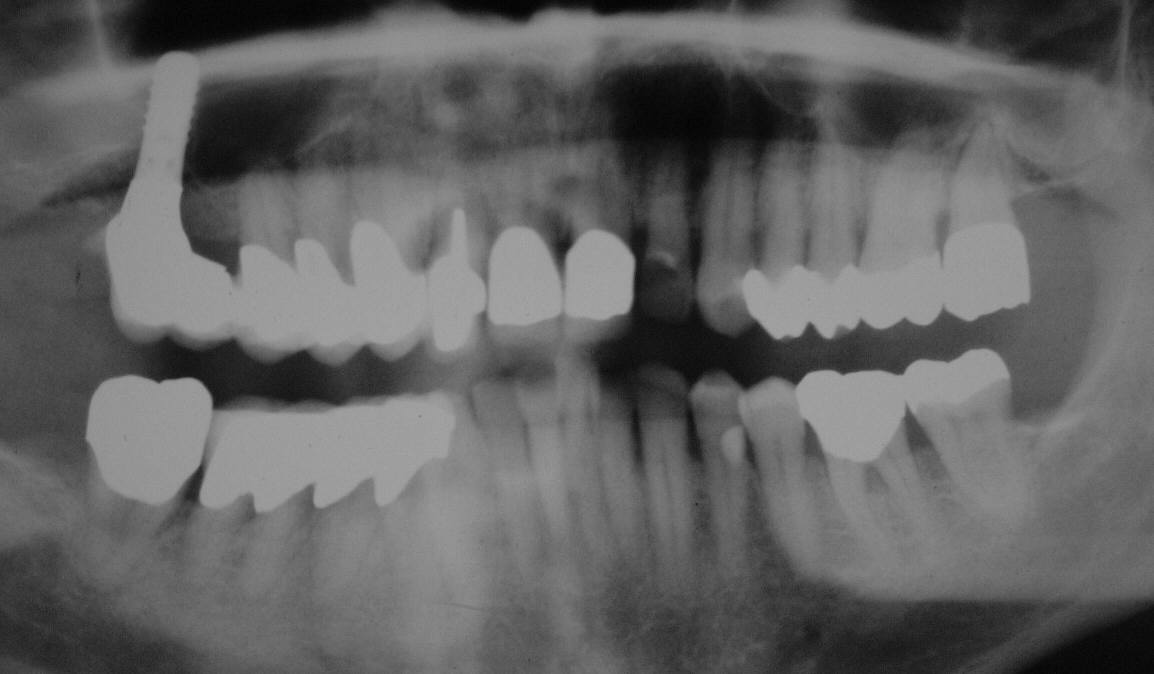

Kontroll-OPT vor Reentry-Op im Juli 2002. Der ehemalige Stollen koronal des Implantates ist vollständig knöchern verschlossen (Klick!)

Das Cerasorb ist vollständig resorbiert und durch eine röntgenologisch knochendichte Struktur ersetzt (Klick!)